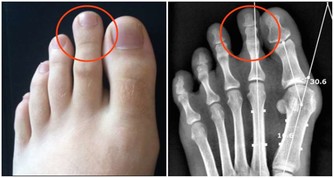

石原結實研究得出:你的身體有了問題,不要擔心體重、血液和血壓檢查的結果,請先量一量你的體溫。看看你的體溫是否降低了。可能你的體溫只有35度左右吧。低體溫是諸多疾病的根源。